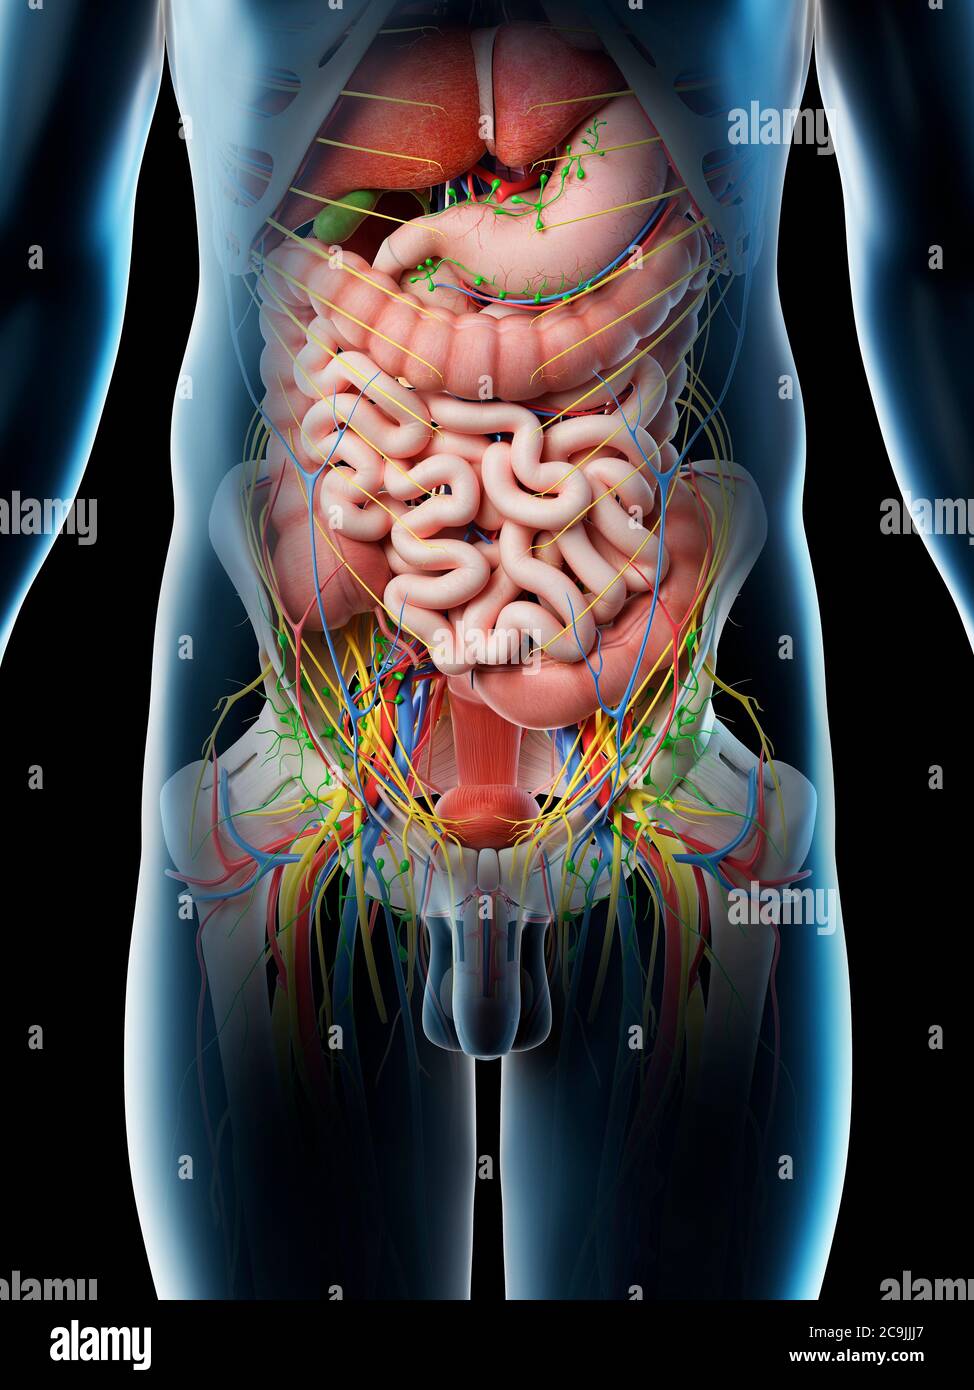

abdomen anatomy model Medically accurate illustration of the abdominal anatomy stock photo

anatomychart101.storage.googleapis.comIllustration Of Human Abdominal Anatomy In Body Silhouette. — Digitally

anatomychart101.storage.googleapis.comIllustration Of Human Abdominal Anatomy In Body Silhouette. — Digitally

schematicfixblagged.z22.web.core.windows.netMale Abdominal Organs, Computer Illustration Stock Photo - Alamy

schematicfixblagged.z22.web.core.windows.netMale Abdominal Organs, Computer Illustration Stock Photo - Alamy

Male Abdominal Organs, Computer Illustration Stock Photo - Alamy

Male Abdominal Organs #1 Photograph By Sebastian Kaulitzki/science

fineartamerica.comorgans abdominal kaulitzki

fineartamerica.comorgans abdominal kaulitzki

Medically Accurate Illustration Of The Abdominal Anatomy Stock Photo

www.alamy.comabdominal medically accurate

www.alamy.comabdominal medically accurate